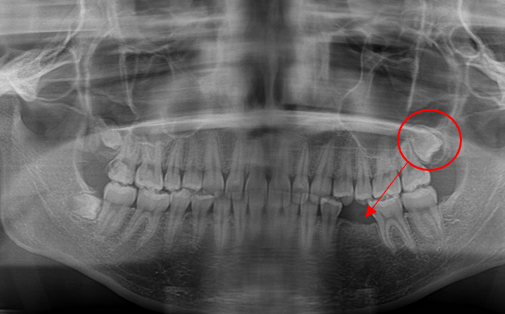

Before

After

左下の親知らずの歯を移植の症例です。